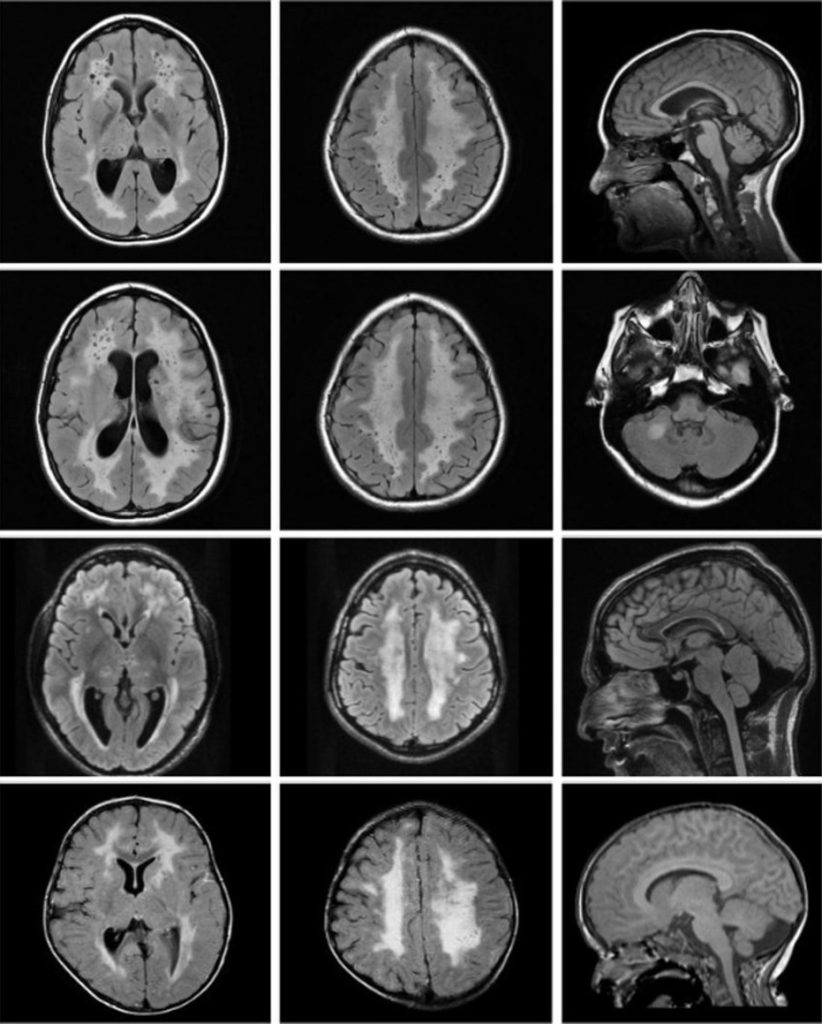

A pesar de que toda la IA es algoritmos matemáticos, si no sabés nada de matemática, no importa. No vas a ver ni una sola fórmula. La idea es compartir cómo logramos que un sistema informático interprete los latidos de tu corazón o “vea” algo en una imagen médica que al ojo humano se le podría pasar. Pensá que un algoritmo en una computadora (particularmente, uno de IA) puede analizar cientos de imágenes sin cansarse, lo que a un profesional médico podría ocurrirle. Y ya sabemos que, cuando estamos cansados, podemos cometer más errores u omisiones.

Por ejemplo, a un algoritmo de IA le podemos mostrar radiografías que corresponden a personas sanas, con neumonía viral o con neumonía bacteriana y modificar matemáticamente cómo trabaja para que “aprenda” a reconocer esos estados en nuevas imágenes. Como ves, necesitamos datos que previamente han sido etiquetados por expertos. Siempre, hasta el momento, es necesaria una etapa en la que el conocimiento humano es el protagonista.

- Otros equipos obtienen imágenes por medios físicos como los rayos X (radiografía o tomografía) o el magnetismo y señales de radio (resonancia magnética).

Sin abandonar el enfoque anterior, hoy las computadoras nos permiten trabajar con la IA Conexionista, basada en datos. Este fue el gran salto. En vez de darle reglas fijas a la computadora, le damos ejemplos. Miles de ejemplos. Es exactamente como cuando le enseñás a un niño a distinguir un perro de un gato. No le das un manual de anatomía; simplemente le señalás fotos y decís: “esto es un perro”, “esto es un gato”. Después de ver muchas fotos, el cerebro del niño (y análogamente un algoritmo de IA, que puede ser una red neuronal) aprende solo a identificar los patrones no triviales que diferencian a uno del otro.

En nuestro laboratorio, esos “perros y gatos” son señales o imágenes. La IA se entrena mirando datos y aprendiendo qué es “lo normal” y qué es “lo patológico”. Es un cambio de paradigma total que hoy es una realidad.